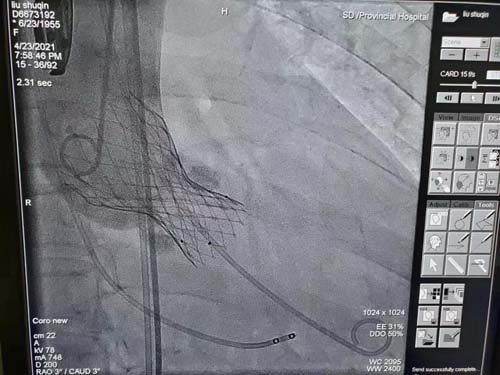

近日,伟德1949官方网站(山东省立医院)东院区心内科顺利完成首例急症经导管主动脉瓣置换手术(TAVR)。

心内科主任苑海涛得悉患者情况后,立即协调相关科室讨论,判定保守治疗无望,外科手术无法耐受,急症经导管主动脉瓣置换术(TAVR)是挽救患者生命的唯一方法。经导管主动脉瓣置换术(TAVR)通过股动脉送入介入导管,将人工心脏瓣膜输送至主动脉瓣区打开,从而完成人工瓣膜置入,恢复瓣膜功能。手术无需开胸,因而创伤小、术后恢复快。然而这种介入手术的操作非常复杂,需要心脏内科、心脏外科、医学影像科室、麻醉科和重症监护等多科室的团结协作,事先制定周密的诊治计划。

心内科副主任王勇和李少华、张明伟医生组成的手术团队,在北京阜外医院王旭教授指导下,顶着巨大的压力,顺利植入人工瓣膜。患者血氧饱和度从术前70%快速上升至91%,血压从术前大量泵入去甲肾上腺素维持在80/50mmHg到术后少量升压药即可维持在112/65mmHg,主动脉瓣跨瓣压差基本消失,且只有极少量返流,手术圆满完成。